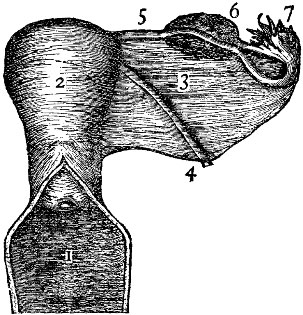

Fig. 2 gives a very good idea of the shape and general structure of this bony framework; while a careful study of Fig. 3 will enable one to form a very correct idea of the relative size and position of the various parts contained in this framework.

The Ligaments of the Uterus.—By referring to Fig. 5 it will be seen that there are on each side of the uterus flat bands of tissue known as "broad ligaments." These ligaments are attached to the sides of the pelvic cavity, and aid greatly in holding the uterus firmly in place. There are also other ligaments concerned in this same work, although the broad ligaments are most important. The illustration also shows the walls of the vagina cut open, in order that the position of the mouth of the uterus may be easily seen.

| Fig. 4. This illustration shows the cavities in a uterus which has been pregnant. 1, the vagina; 2, cavity of the neck of the uterus; 3, cavity of the body, above which is the fundus of the uterus; 4, Fallopian tubes, extending to the ovaries. | Fig. 5. The female generative organs. 1, the vagina; 2, uterus; 3, broad ligament of left side; 4, a smaller ligament; 5, Fallopian tube; 6, ovary; 7, fringed end of Fallopian tube. |

Fallopian Tube.—Figs. 4 and 5 show that there is given off from each side of the upper part of the uterus a tube. This is called the Fallopian tube.

Each tube is about four inches long. Near the uterus its cavity will just admit an ordinary bristle; but near its free end, at the ovary, it is as large as a goose-quill.

It is a peculiar tube in that it terminates in a number of fringe-like processes, one of which is always attached to the ovary itself.

Object of This Tube.—The Fallopian tube conveys the sperm of the male from the uterus to the ovary, and also takes the germ-cell (or ovule, or egg) from the ovary to the uterus.

When a ripe egg is about to be discharged from the ovary, one of these fringe-like processes of the Fallopian tube grasps it and receives it into the mouth of the tube, whence it is conveyed directly into the uterine canal.

Ovary.—On each side of the uterus and in each side of the pelvic cavity is an ovary. It is about one and a half inches in length, three-fourths of an inch in width, and one-third of an inch in thickness. It weighs from one to two drachms, and is an elongated, oval-shaped body.